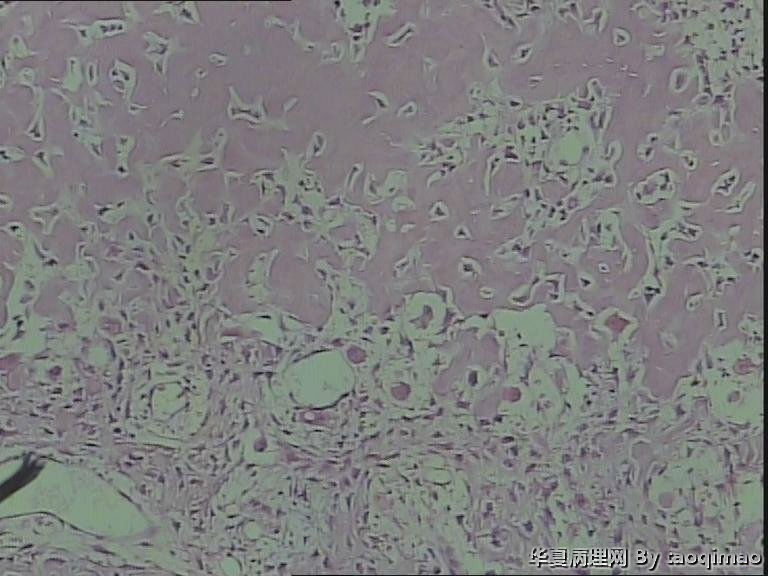

肋骨肿物,求助

这是比较容易取下来的部分,肋骨内部的肿瘤还在制片中

这是一部分容易取下来的肿瘤,其余部分还在脱钙中

患者女,31岁,胸部CT第八肋骨肿瘤,肿物在肋骨内突出骨外膜,大小2.3X1.5.切面灰白质韧

骨母细胞瘤。矿化不均要除外骨母细胞型骨肉瘤,虽然肿块小了点。还是找找核分裂,看看X线的好。

老师不考虑骨样骨瘤么?X线说偏向良性肿瘤